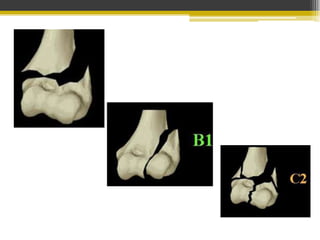

Clasificación Ao

• Tipo I: Fx bicondílea sin conminución

• Tipo II: Fx bicondílea con conminución

articular

• Tipo III: Fx bicondílea con conminución

articular y en columnas óseas supracondíleas.